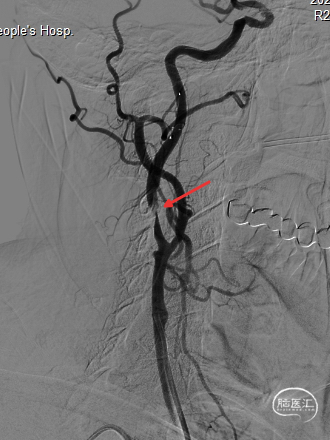

4.0*30mm通桥白驹®球囊以6atm扩张(左图箭头),扩张完毕后多角度造影显示狭窄交前明显改善(中图箭头处),扩张完毕后支架置入(右图箭头处)。

扩张完毕后多角度造影显示狭窄较前明显改善(箭头处)。

撤出保护伞观察10分钟复查造影,无弹性回缩,狭窄明显好转,血流明显改善(箭头处),结束手术。